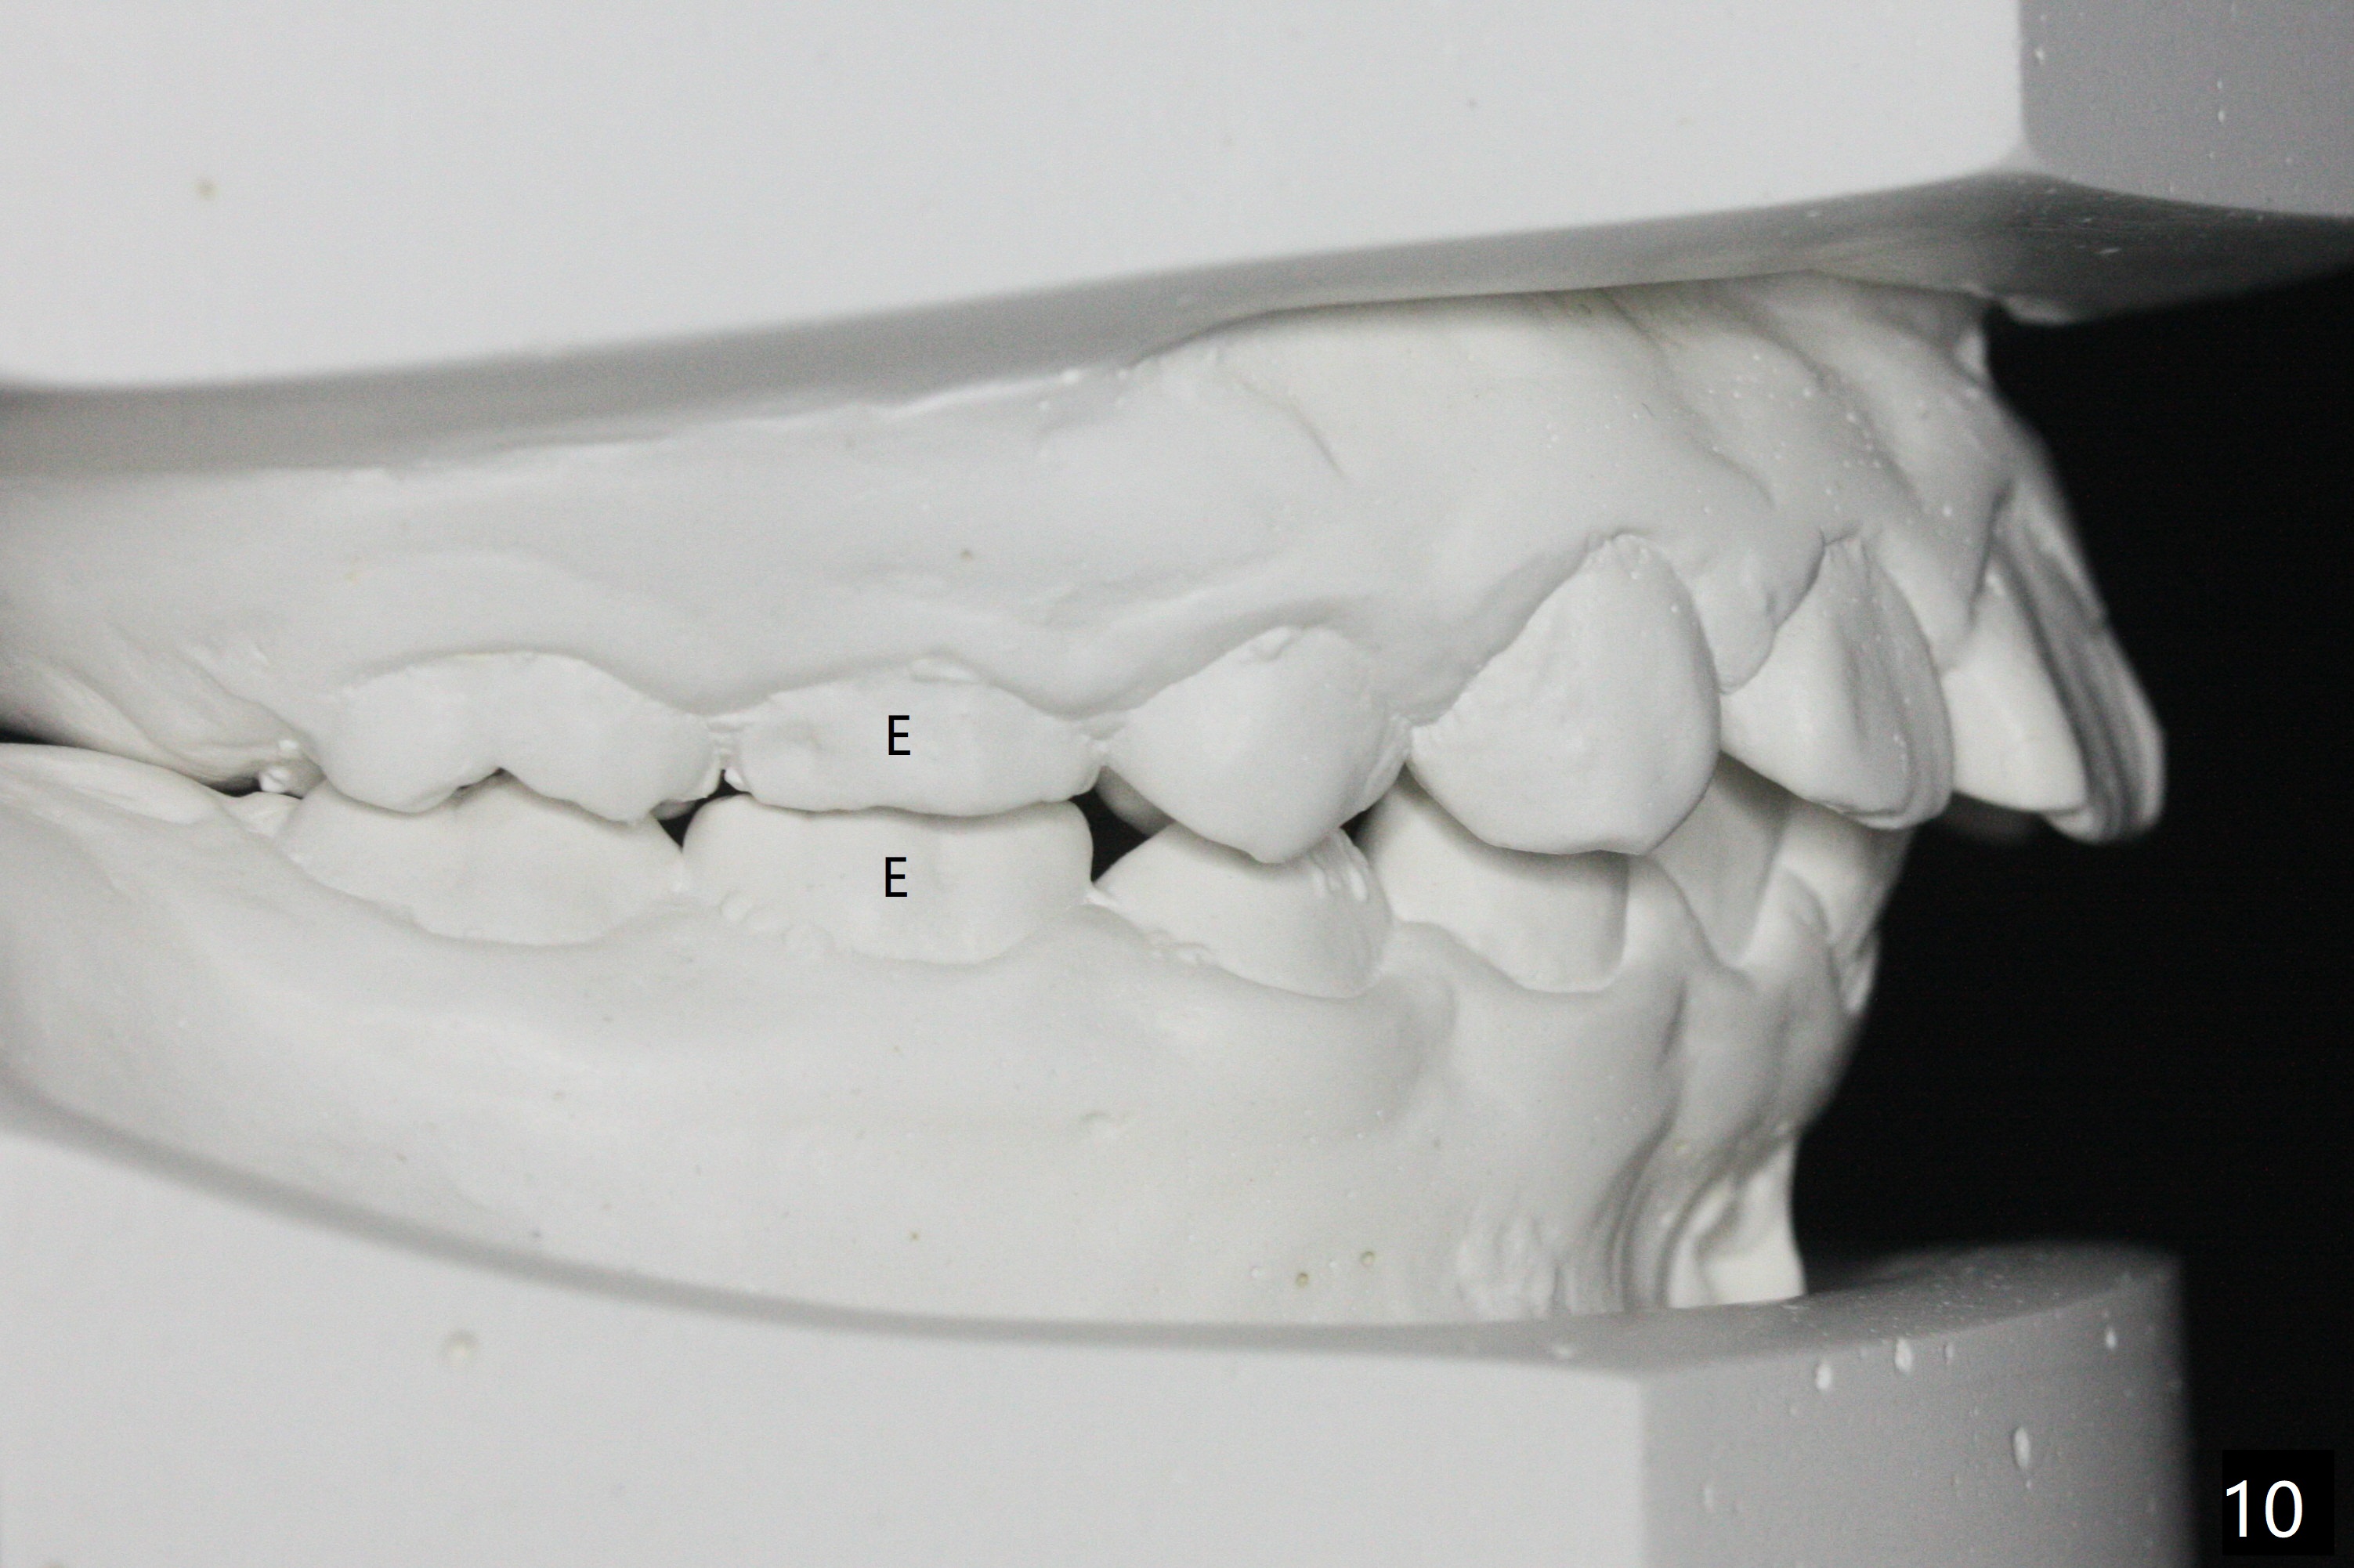

The mother of a 10-year-7-month old man requests treatment for the crowding lower incisors (Fig.14). The canines and molars are Class II by a half of a tooth (Fig.7,9,10,12). The dentition is mixed with E retention (Fig.13,14,16). Orthodontic treatment will start before E exfoliation for alignment and establishment of Class I occlusion as much as possible by distalizing U6s. Fine adjustment for intedigitation will be made when E exfoliate.